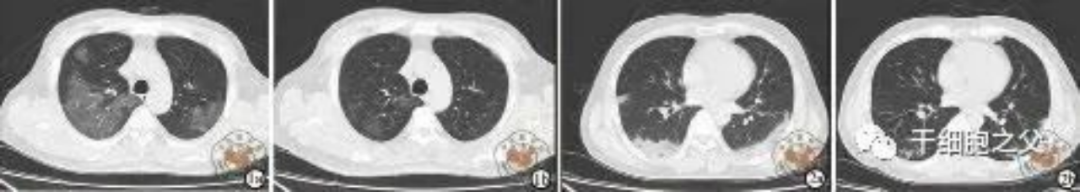

如圖所示,1a-1b:細胞輸注后,炎癥指標改善,復查胸部CT提示雙肺病灶較前吸收,呼吸道癥狀改善,新型冠狀病毒核酸檢測連續2次陰性,治愈出院。圖2a-2b:2次干細胞輸注后炎癥指標改善,復查時(shí)氧合指數升高至301 mmHg,胸部CT提示雙肺病灶較前吸收,患者呼吸道癥狀改善,新型冠狀病毒核酸檢測連續2次陰性,治愈出院。